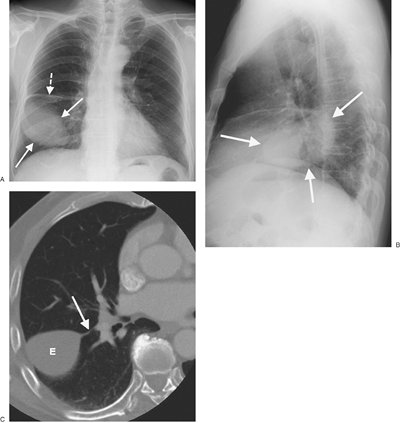

FIGURE 9-11. Malignant pleural effusion. A: PA chest radiograph of a 62-year-old woman with metastatic breast cancer who has had a right mastectomy and axillary node dissection (note surgical clips in right axilla; arrows) shows apparent elevation of the right hemidiaphragm. B: Lateral chest radiograph also shows apparent elevation of the right hemidiaphragm (arrows). The left hemidiaphragm is easily identified (arrowheads), as it is just superior to the stomach bubble. C: CT shows a large right pleural effusion (E) and metastatic breast cancer infiltrating the right chest wall (arrows). D: CT at a level inferior to (C) shows a metastatic soft tissue mass to the mediastinal pleura (arrow) and thickening of the mediastinal pleura (arrowheads).